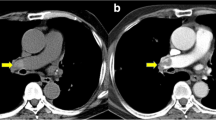

All CT images of the training cohort were analyzed and evaluated by two blinded and independent readers (I.V., A.K.; both with 4 years of experience in cardiovascular imaging). The two readers measured the attenuation (in HU) using a ROI (10 mm in diameter) in the RV and LV on axial CT images (Fig. 2), carefully avoiding the inclusion of the mitral or tricuspid valves, papillary muscles, the moderator band, and ventricular trabeculae. Each reader independently selected the specific axial slice for the measurements. The HU difference of the values in the RV and LV (subsequently called HUdiff) and the ratio between the two values (RV/LV, HUratio) were calculated.

Attenuation measurements in the right and left ventricles. Panel a shows attenuation measurements in a 65-year-old female patient without pulmonary embolism demonstrating higher attenuation in the RV than in the LV (RV: 523 HU, LV: 236; HUratio: 2.22, HUdiff: 287). This patient was subsequently diagnosed with acute heart failure and a left ventricular ejection fraction of 48%. Panel b shows attenuation measurements in a 70-year-old female patient without pulmonary embolism demonstrating comparable attenuation in both ventricles (RV: 364 HU, LV: 321 HU; HUratio: 1.13, HUdiff: 43). This patient was diagnosed with acute exacerbation of chronic obstructive pulmonary disease